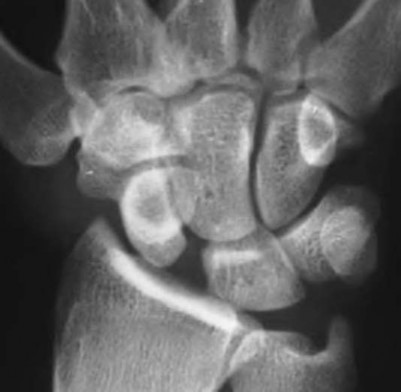

A 20-year-old park ranger trips and falls onto his right wrist with the wrist in extension and pronation. The local urgent care orders both radiographs and a CT, which you review and determine to be normal. The patient complains of ulnar-sided wrist pain. On exam, his tenderness is localized to the fovea. Ulnar deviation also causes him pain. There is no snapping sensation with wrist supination, flexion, and ulnar deviation. He otherwise has 5/5 strength to his first dorsal interosseous muscle with 4mm static two-point discrimination on the ulnar side of the 4th digit. Which of the following injuries is most likely responsible for his symptoms and exam?